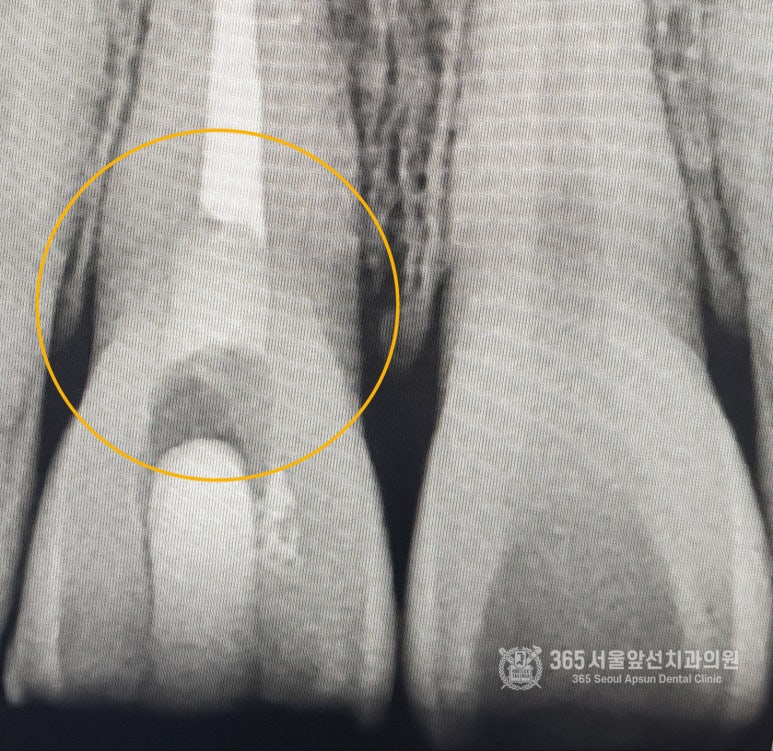

안녕하세요.시민공원역에 위치한 365서울앞선치과입니다. 오늘 소개해드릴 치료 증례는 낙상으로 인하여 치아가 부러져 치료를 받지 않고 방치를 하셨다가 치아 신경이 손상되어 검게 변해버린 케이스인데 처음 저희 치과를 찾아주셨던 당시 구강내 모습입니다. 촬영일시 : 2024.06.06 치아 파절로 인해 치아 신경이 손상되어 치아가 검게 변한 모습도 관찰됩니다. 노란색 동그라미 부위처럼 고름이 잇몸으로 나오고 있는 것도 보실 수 있습니다. 이러한 경우 신경치료를 통해 먼저 신경의 문제를 해결하고, 이후 검게 변한 치아를 치아미백이나 보철물 제작을 통해 해결해드리면 되겠습니다 촬영일시 : 2024.06.21 고름이 새어 나오던 자리는 신경치료를 통해 해결되어 고름주머니가 사라진 것을 보실 수 있습니다. 부러진 치아 부위 아래로 하얗게 보이는 것은 신경치료 과정에서 사용되는 임시충전제입니다. 여러번의 내원을 통해 신경 치료가 이루어지기 때문에 임시충전제가 탈락되지 않도록 주의가 필요합니다. 신경치료가 완료되었고, 치아미백을 통해 옆치아와 색상을 맞추는 과정을 진행합니다. 촬영일시 : 2024.07.20 색상도 밝아졌고 치아의 형태도 레진을 이용하여 옆치아와 조화를 이룰 수 있게 만들었습니다. 환자분께서 매우 만족하셨던 기억이 납니다. 오늘은 부러진 치아를 신경치료를 통해 살리고, 어두워진 치아 색상을 미백으로 밝게 해주면서 레진을 이용하여 형태까지 맞춰서 치료한 증례를 소개해드렸습니다. 지금까지 치아를 소중히 여기는 시민공원역역치과 365서울앞선치과의원이었습니다. 365서울앞선치과의원은 365일 늘 가까운 서울대학교 치과병원을 지향합니다! 감사합니다. [ 치료기간: 2024년 6월6일~2024년 7월20일 ] ※365서울앞선치과의원의 모든 포스팅은 각 진료과 의료진이 직접 작성합니다. 365서울앞선치과의원 블로그의 임상 케이스 게시물은 환자분께 의학적으로 정확하고 상세한 정보를 드리기 위해 각 진료과 의료진이 직접 작성하며, 모든 증례 사진은 본원 의료진이 직접 시술한 증례를 촬영한 것으로, 의료법 제23조, 제56조에 의거하며 환자분의 동의를 얻어 포스팅에 사용하였습니다. 또한 해당 케이스는 본 환자분의 치료 결과이며, 환자 상태에 따라 치료의 결과는 달라질 수 있습니다. |